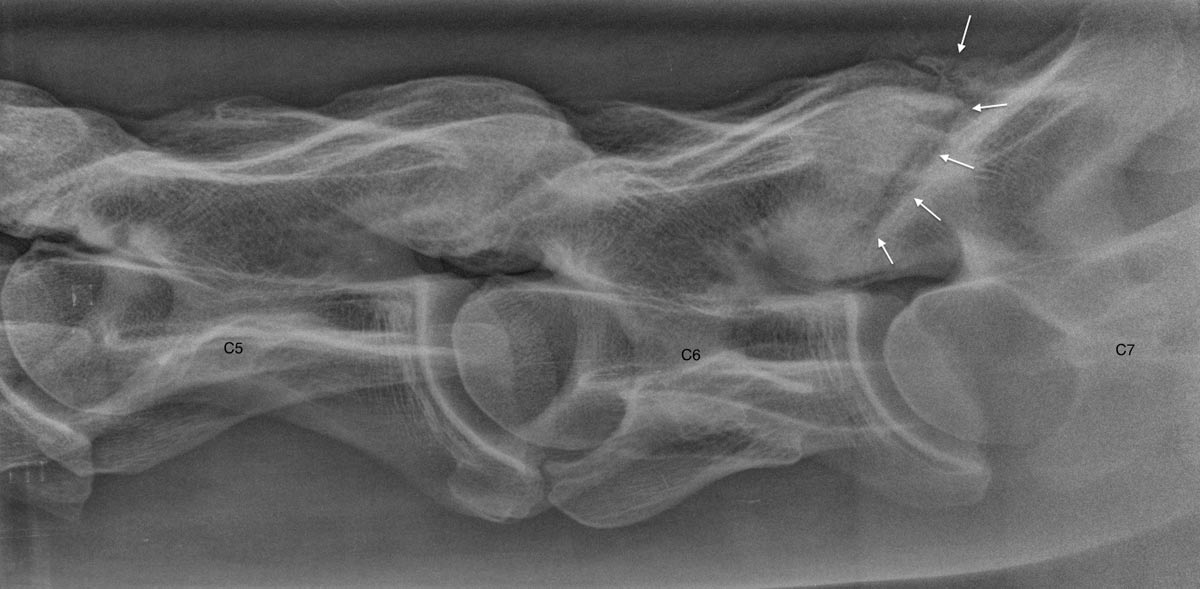

La radiographie est une technique ancienne qui connaît encore une grande évolution dans notre monde digital moderne. EquiSound dispose de 2 systèmes de radiographie digitale combinés à une machine à rayons X puissante de 80.000 Watts (80 kV). Nous pouvons produire des radiographies du cheval complet d’excellente qualité, tête, encolure et dos inclus.

Grâce à notre appareil radio portable et notre système DR, nous pouvons également offrir un service mobile et fournir des images de qualité chez vous lorsque votre cheval ne peut pas être transporté vers la clinique.